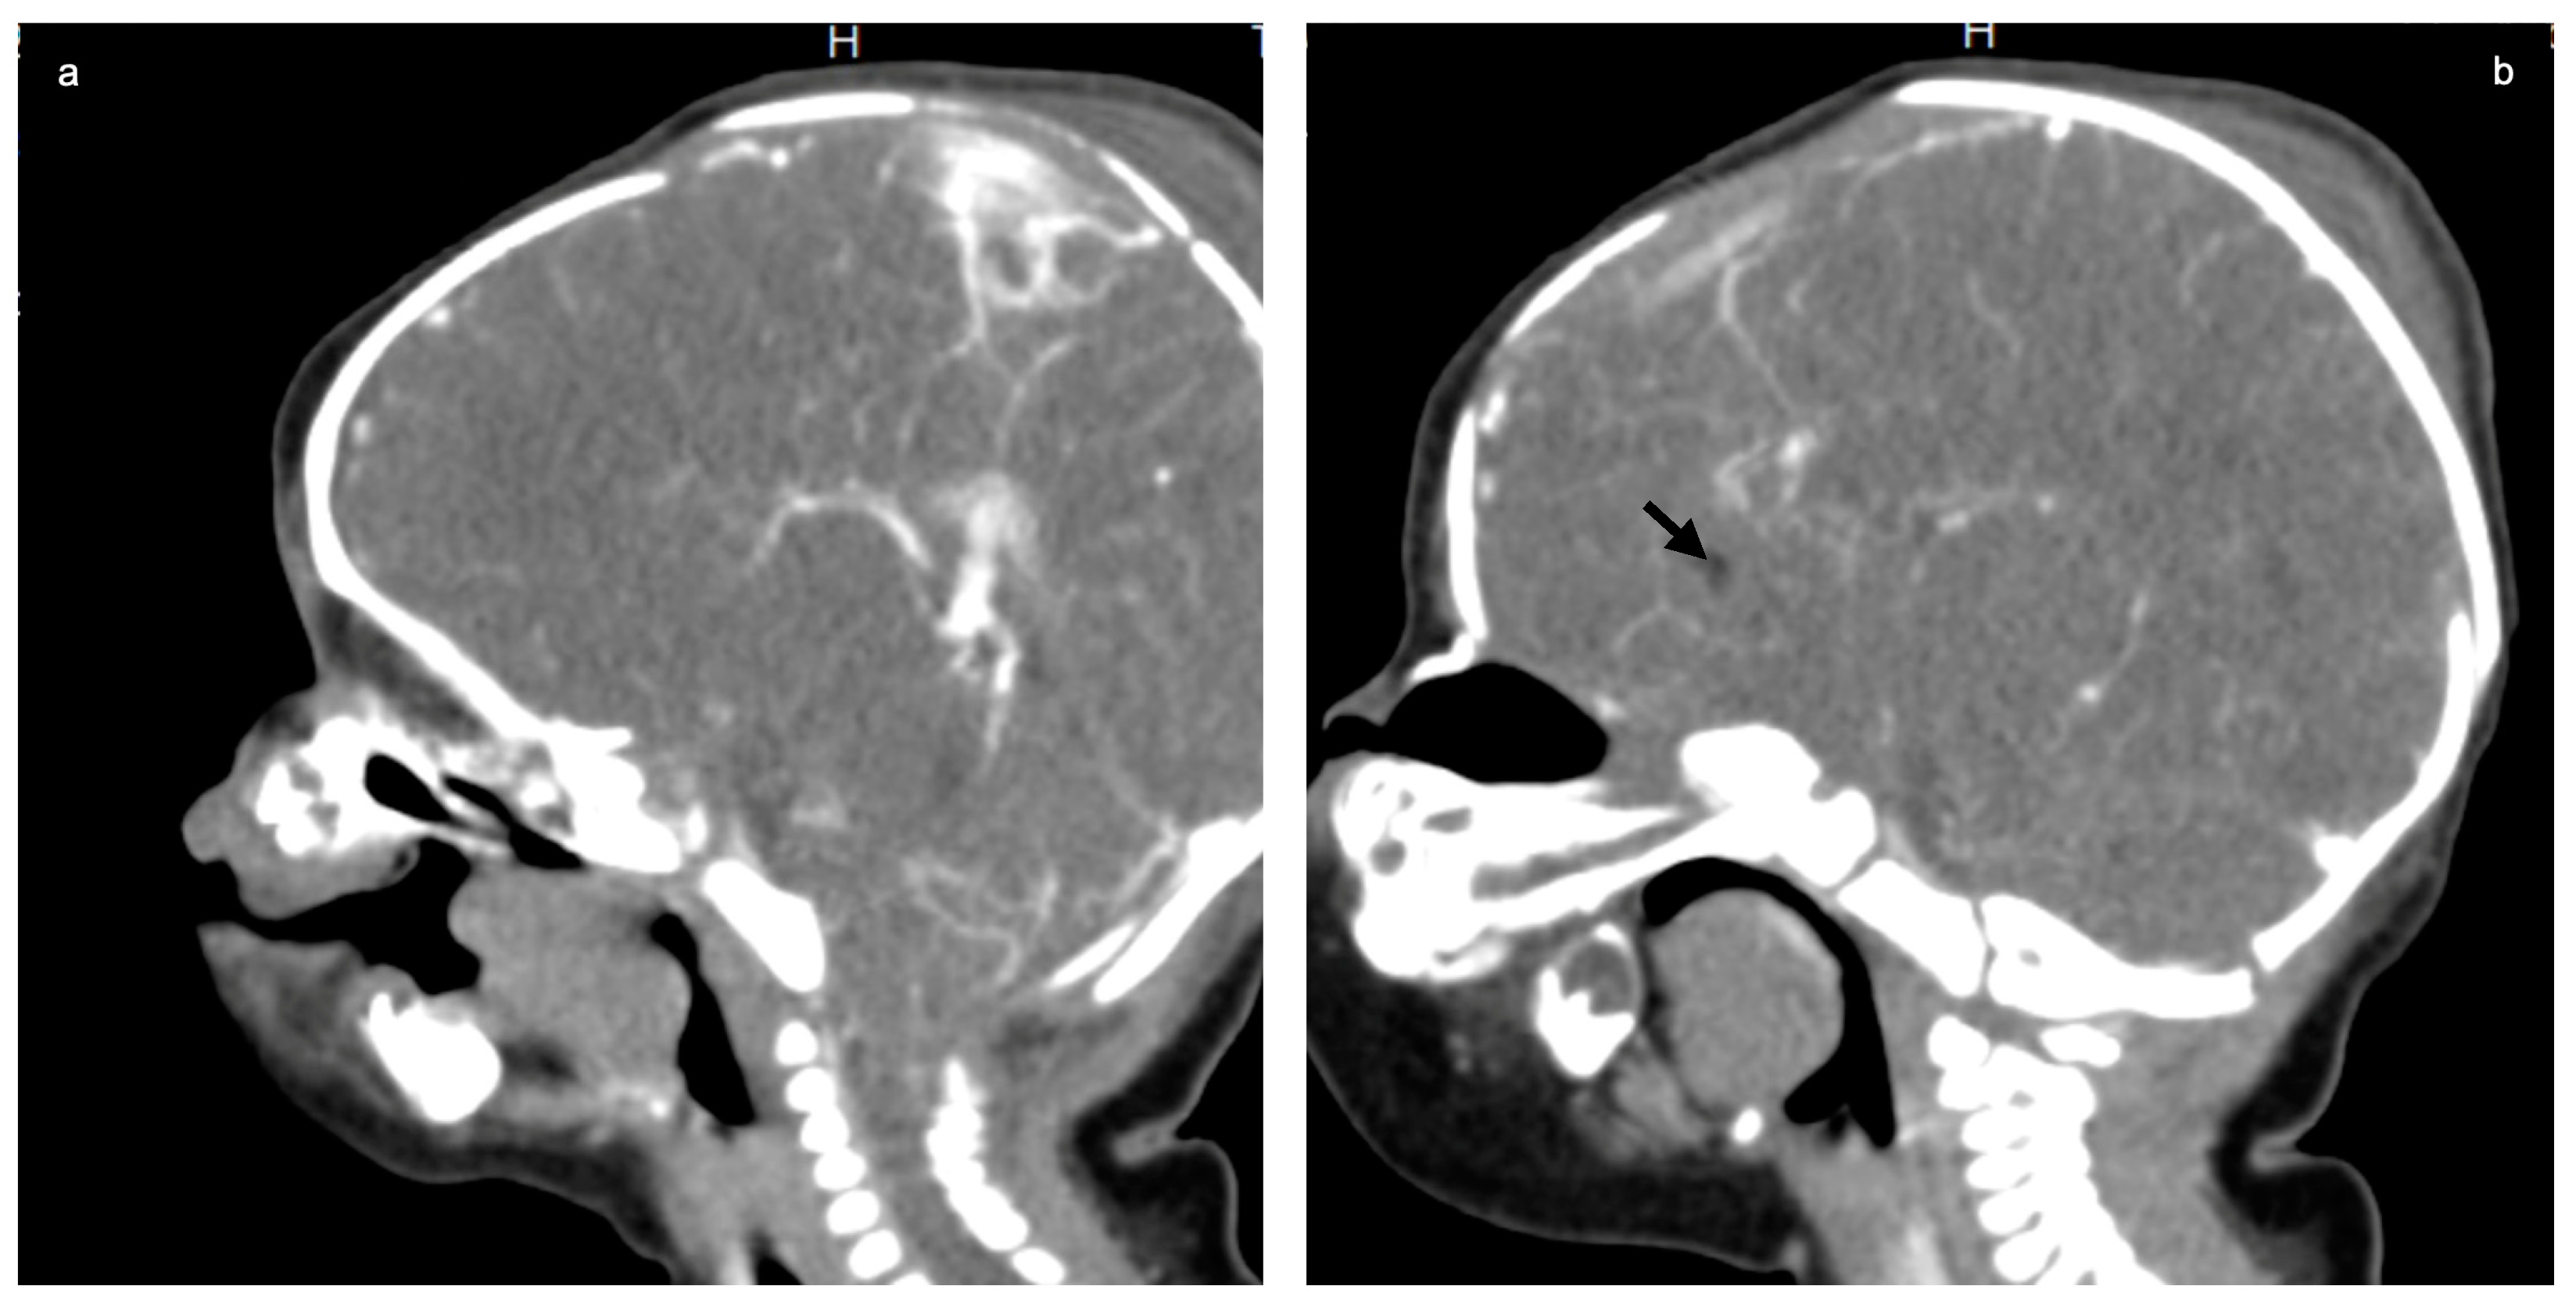

The following tests were carried out: brain ultrasound, skull X-ray, and head and neck CT scan. The brain ultrasound showed an enlargement of the third ventricle, and the corpus callosum was not detectable; since the examination was performed with an inappropriate probe (only the adult convex probe was available), it was not possible to visualize the cerebral cortex (Figure 3). On the skull X-ray, complete disorganization of the axillary and mandibular bones was revealed (Figure 4). To understand the malformation more precisely, a cranial CT scan was performed, which clarified the picture of bony disorganization of the maxillofacial complex; this examination revealed the presence of duplication of the mandible and, partially, the maxillary bones and the presence of a double opening of the oral cavity (Figure 5). Through CT image analysis of the central nervous system, it was possible to confirm the agenesis of the corpus callosum and the presence of a small anterior midline lipoma, a small posterior cranial fossa with the extension of the tonsils beyond the level of the foramen magnum was also found (Chiari I malformation) (Figure 6).

We emphasize that as many as 96% of these cases also have brain malformations. In particular, focusing on agenesis of the corpus callosum, it is described in only three other reports [15,19,20] besides ours; however, none of these present a midline lipoma and a Chiari I malformation.

Figure 6. Brain contrast CT (sagittal MPR): agenesis of the corpus callosum (a) with a small anterior midline lipoma (b); black allow and small posterior fossa with cerebellar tonsillar ectopia, the tonsils extending below the level of the foramen magnum (a).